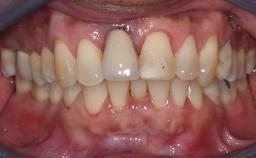

The patient presented with a failing tooth-supported fixed dental prosthesis with cantilever extension replacing the right maxillary central incisor. His chief presenting complaint was poor esthetics, in particular the dark discolored margin around the abutment tooth, the maxillary left central incisor. He reported a history of trauma at a young age, which necessitated the replacement of his maxillary right central incisor as well as root canal therapy of the adjacent left central incisor. The existing prosthesis had been in situ for over 20 years. The initial periapical radiograph displayed good proximal bone levels at the adjacent teeth and a wide incisive canal, which was a concern. The left central incisor presented a very wide root canal treatment with compromised radicular dentin thickness, which was a consideration in the decision between a new tooth-supported fixed dental prosthesis vs. an implant-supported prosthesis. After a lengthy discussion on the risks and benefits of both treatment options, the patient decided on a single-tooth implant replacement.